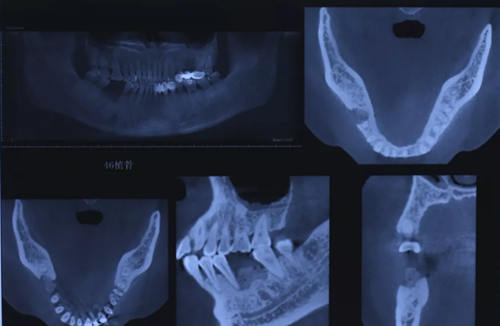

7、術(shù)后CBCT檢查

術(shù)后CBCT顯示拔牙窩內(nèi)充滿(mǎn)植骨材料。

(攝于2016年8月31日)

10、CBCT檢查

CBCT檢查測(cè)量缺牙區(qū)可用骨高度14.40mm,骨寬度6.72mm。

(攝于2017年2月15日)